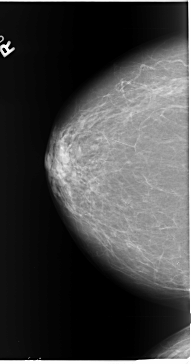

B_3089_1.RIGHT_MLO

RIGHT_CC LINES 5816 PIXELS_PER_LINE 3048 BITS_PER_PIXEL 12 RESOLUTION 50 NON_OVERLAY

RIGHT_MLO LINES 5880 PIXELS_PER_LINE 3576 BITS_PER_PIXEL 12 RESOLUTION 50 NON_OVERLAY